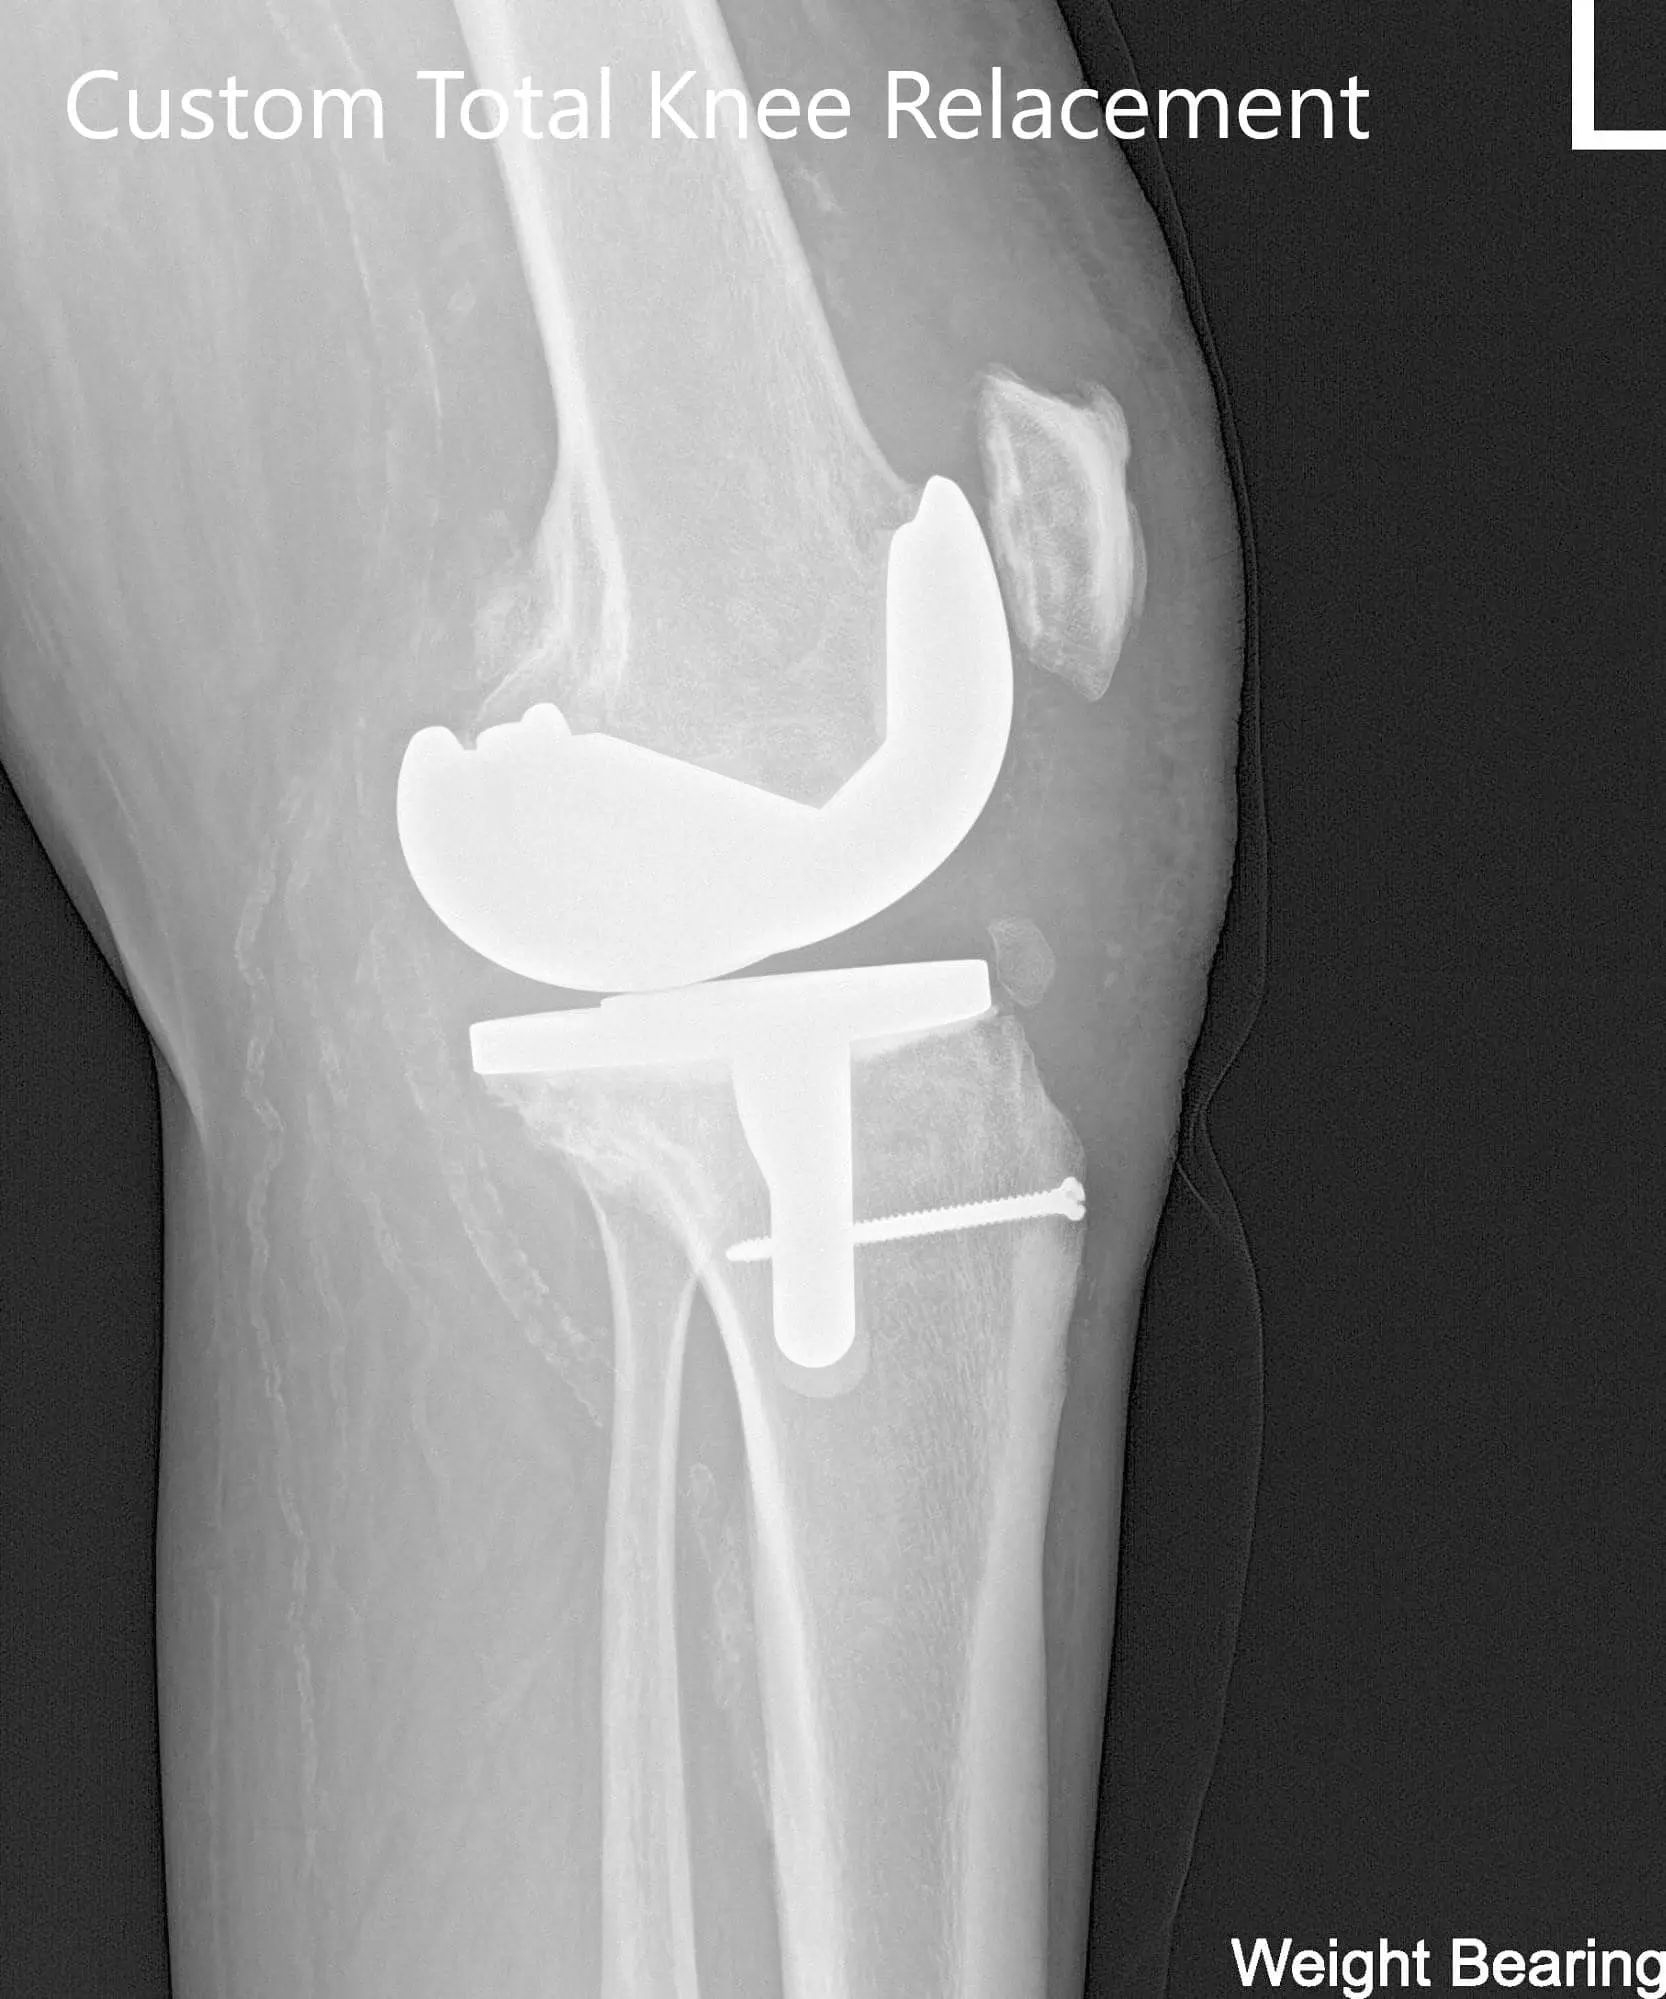

Postoperative X-ray of the left knee showing AP and lateral viewsPostoperative X-ray of the left knee showing AP and lateral views - img 2

Postoperative X-ray of the left knee showing AP and lateral views

The patient had an expedited post-operative recovery. She was bearing weight walking with support the same day. Her pain was well managed on medications and she was started on aspirin 325mg BID for deep vein thrombosis prophylaxis. On her subsequent visits, she had her staples removed. Her surgical wound was clean, dry and intact.

She was started on physical therapy and home exercise program regime. The patient was compliant with the regime and demonstrated a full range of motion. She was happily back to work and enjoyed her visits to the supermarket walking. She was able to continue her daily activities and was enthusiastic about the results. She was advised to follow up for the replacement of the right knee.